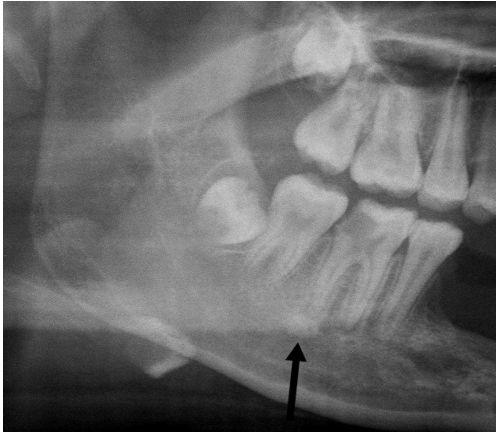

64.關於附圖中箭頭所指之解剖構造,下列敘述何者錯誤? (A)是下顎骨舌側表面上的突起 (B)是geniohyoid muscle附著之處 (C)稱為mylohyoid ridge (D)稱為internal oblique ridge

79.35歲男性因下顎左側後方不適而來求診,經X光檢查如附圖所示,黑色長箭頭所指的病變,最可能為下列何 者? (A)外傷性骨囊腫(traumatic bone cyst) (B) 含齒囊腫(dentigerous cyst) (C)根尖囊腫(radicular cyst) (D)殘餘囊腫(residual cyst)